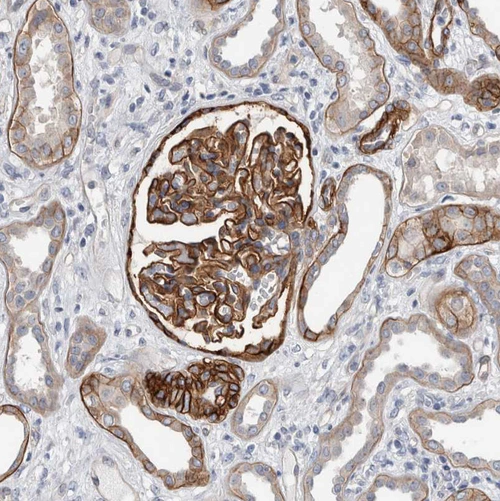

Immunohistochemistry analysis in human fallopian tube and liver tissues using HPA005654 antibody. Corresponding BCAM RNA-seq data are presented for the same tissues.